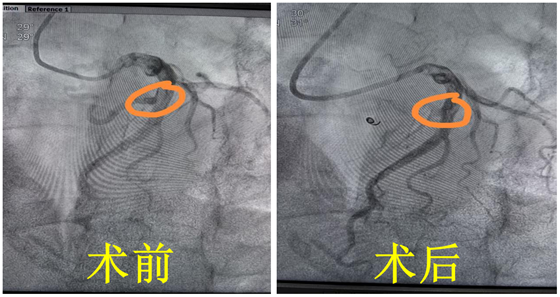

术中,杨国栋、汤金城副主任医师通过一个针眼大小的孔,利用特制微导管将弹簧圈+外科胶送入瘘管,成功将瘘管封堵。经再次冠脉造影显示:瘘管血流消失,提示瘘管封堵成功。